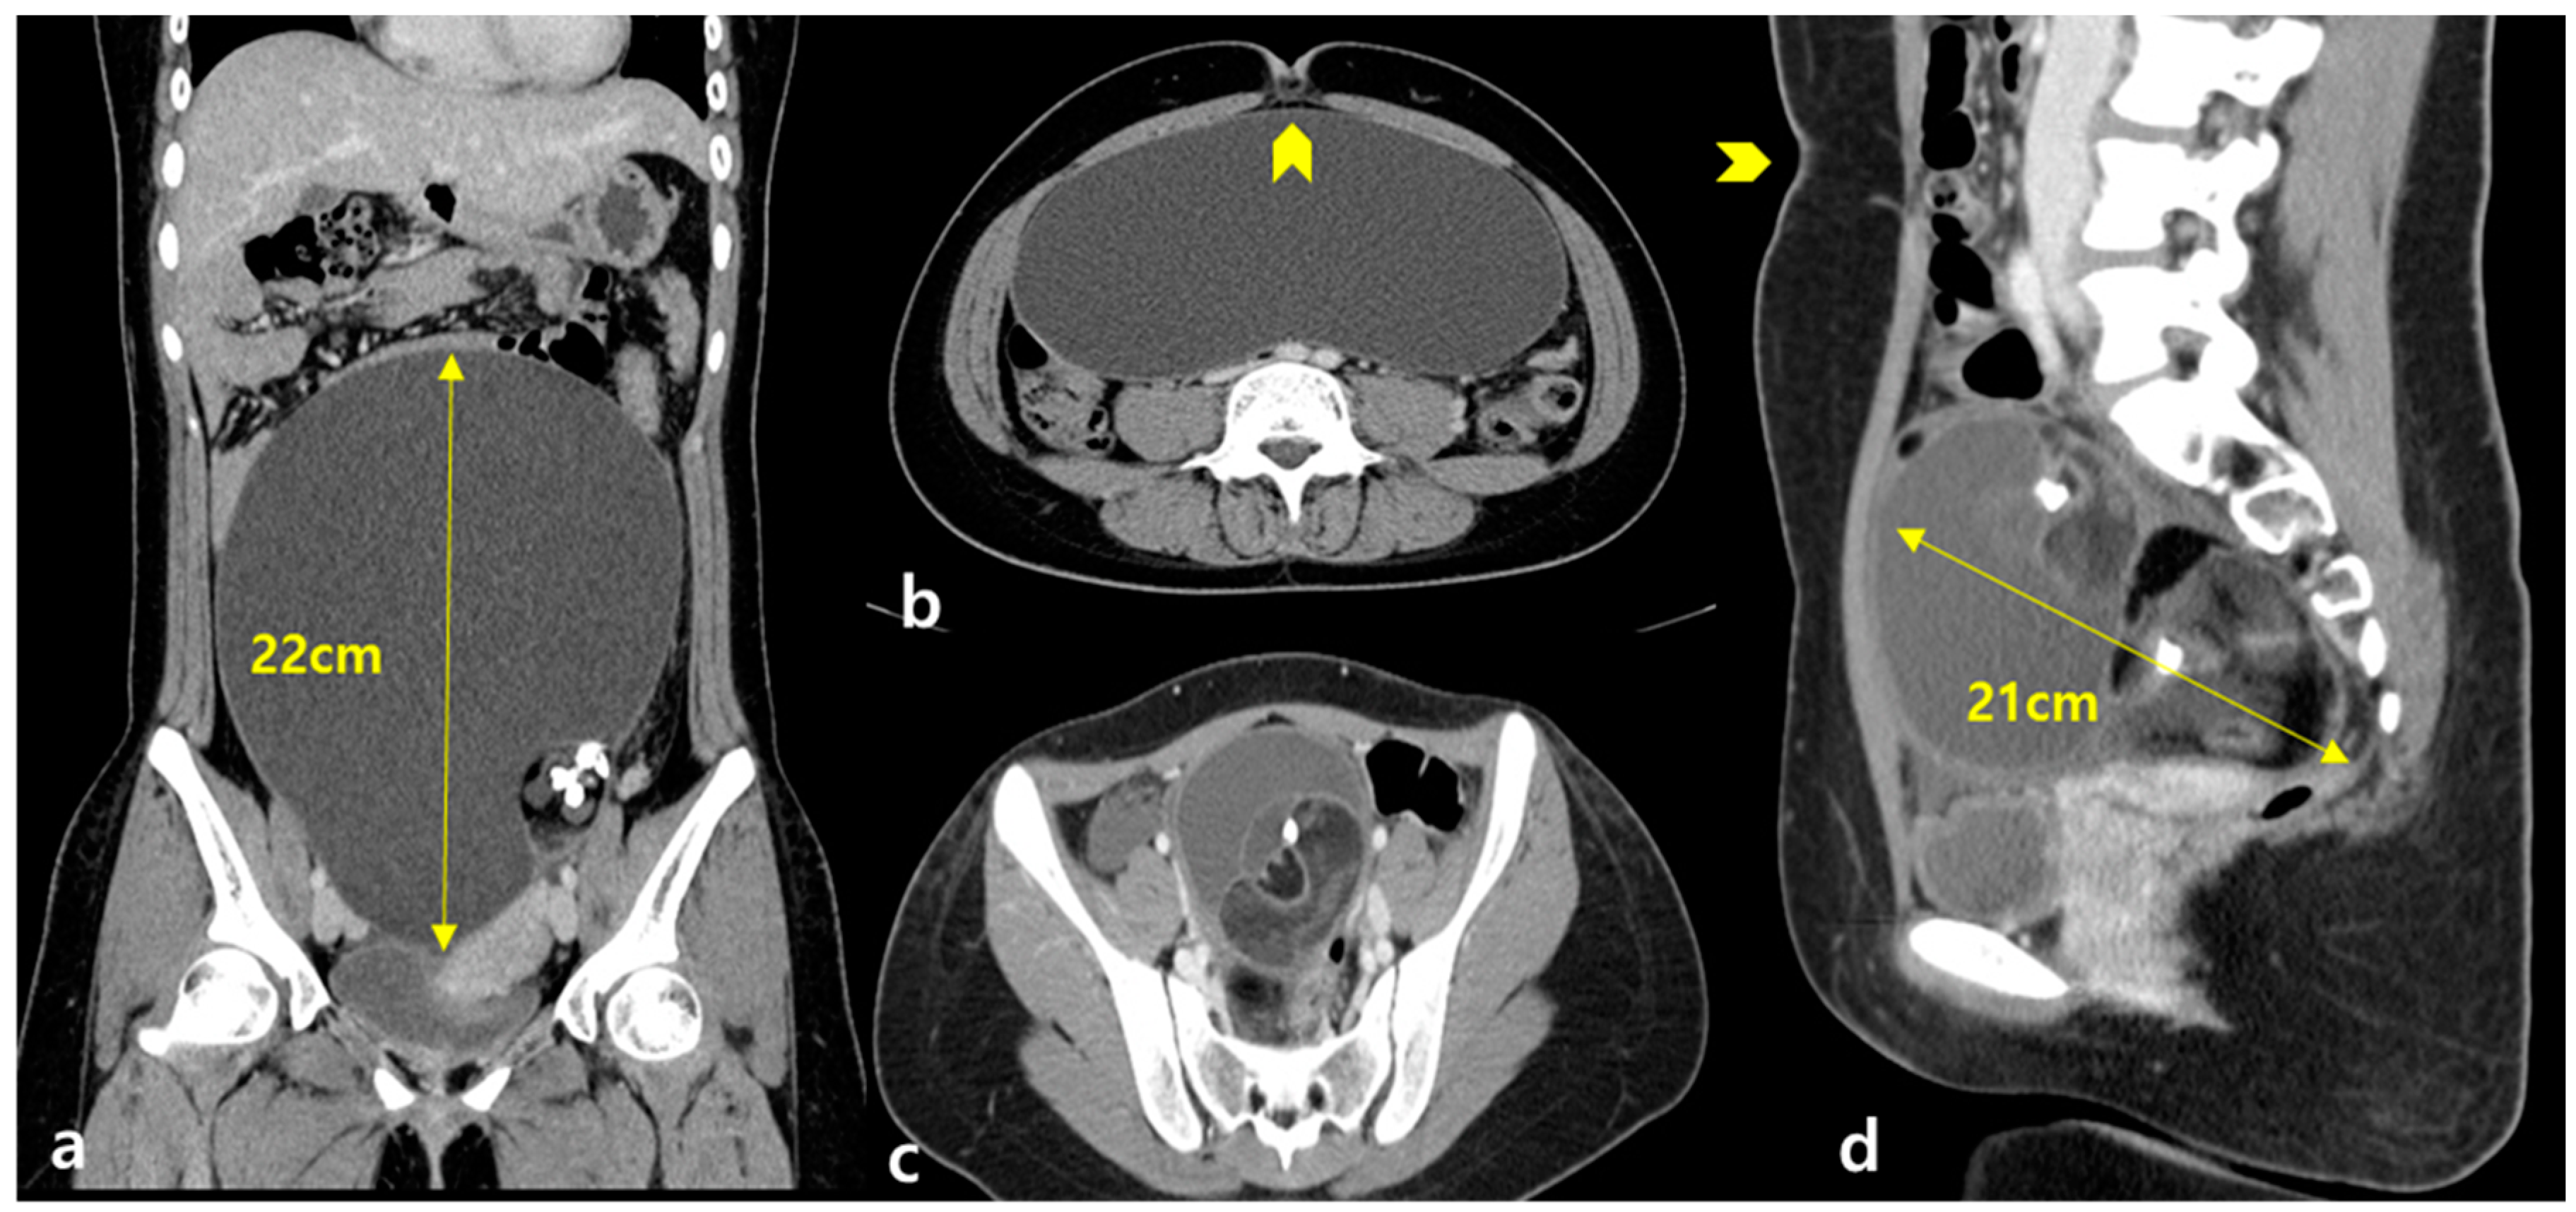

Figure 3. (a) A 17-year-old woman with a huge abdominal mass (Case 1). A coronal view on computed tomography (CT) revealed calcification within a 22 × 20 cm ovarian mass with low signal intensity on T2 weighted imaging (T2WI), suggesting a mature cystic teratoma. (b) An axial view, umbilicus (arrowhead) (c) of an 18-year-old woman with bilateral huge abdominal masses (Case 2). An axial view revealed calcification within a 17 × 15 cm ovarian multi-cystic mass and another 8 × 7 cm mass with low signal intensity on T2WI, suggesting a mature cystic teratoma. (d) A sagittal view, umbilicus (arrowhead).

Seven reproductive-aged patients with huge benign ovarian cysts (>10 cm) underwent single-incision laparoscopic ovarian cystectomy (MCT, n = 4; endometrioma, n = 2; and mucinous cystadenoma, n = 1) (Table 1). The mean patient age was 24.71 ± 6.56 (range 17–37) years, and all patients were of reproductive age with nulligravida. The mean maximal diameter of the mass was 17.71 ± 2.86 (range 13–22) cm, one patient (Case 2) had a bilateral ovarian mass, and the others had a unilateral ovarian mass (Figure 3). None of them had previously undergone ovarian surgery or chemotherapy, which could affect their ovarian reserve. None of them were smokers (Table 1).